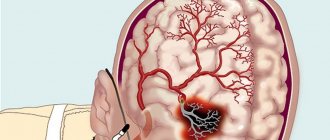

Cerebrovascular diseases are a group of brain diseases caused by pathological changes and focal dysfunction of the brain substance due to insufficient supply of tissues with oxygen and nutrients. There are acute and chronic, ischemic and hemorrhagic processes. In 1987, Khachinsky proposed the concept of leukoaraiosis (from the Greek leuko = white and araios = rarefaction) in order to define abnormalities in the white matter of the brain on CT and MRI scans. Damage can be pinpoint or wider: focal and diffuse. No clinical or pathological relationship has been proposed with this term, so it is merely a term to describe abnormal, fairly common images. That is, we are talking about a type of neuroimage that can be associated with various clinical and pathological situations, heterogeneous in the type of morphological disorders. White matter is nourished by the complex microvascular system of the brain, which consists of small threading arterioles originating from the main arteries of the brain. We are talking about the final arteries of great length and small size. Because of this, the white matter near the ventricles (in the periventricular space) becomes an area of ​​limited vascularity, making it particularly prone to ischemia. The narrowing and reduction of blood flow in the arterioles can lead to a decrease in blood flow to a certain area and, after some time, lead to the appearance of leukoaraiosis. The development of leukoaraiosis usually follows a certain scenario. First, periventricular lesions are observed near the borders of the lateral ventricles (Fig. 1), then, depending on the severity of the problem, new lesions form around the original lesions (Fig. 2).

Fig.1

Fig.2